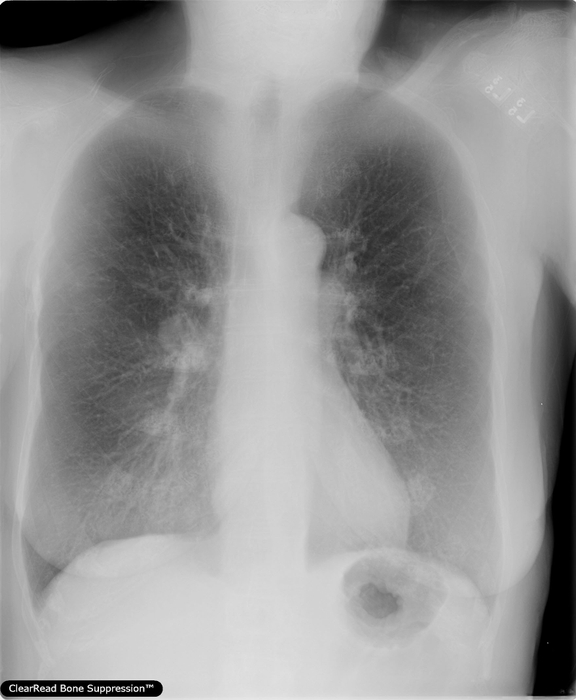

・胸部X線骨組織透過ソリューション/ClearRead BS※1

胸部X線画像の肋骨や鎖骨などの骨組織を透過した画像を生成し、骨組織と重なり検出が困難であった肺結節や異常陰影などの視認性を向上させる。